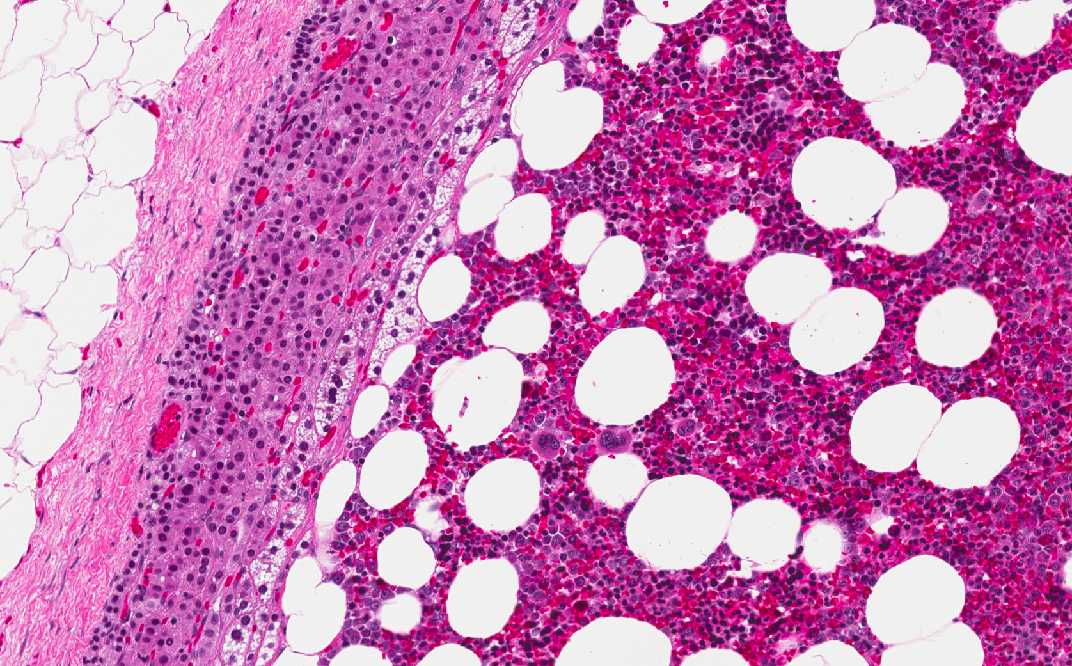

Area 1: A rim of residual adrenal cortex is present (A) which is separated from the tumor (T). The periadrenal fat (F) is separated from the adrenal gland by a thin layer of fibrous tissue which represent the capsule of the adrenal. Note that the residual cells of the adrenal cortex has many foamy cells due to their high fat content and a rich vascular network which is a common features of many endocrine organs.

Area 2: This image is taken from an area where there the tumor has an interface with the residual adrenal cortex. In this area, there are individual adipocytes (A) separated by a backgound of myeloid cells (M). In the high magnification image, you can see a spectrum of myeloid cells in different stages of maturation as well as occasional megakaryocytes.

Histologic Highlights of this Case: This section shows a nodule with a thin capsule which represent the capsule of the adrenal gland. There are some crescents of residual adrenal cortical tissue at the periphery of the nodule. The thin capsule represents the capsule of the adrenal gland. The tumor which is composed of a variable mixture of mature adipocytes and mature myeloid cells with trilineage maturation. Note that even though the tumor is well demarcated from the residual adrenal cortex, there is no fibrous septa or capsule between the tumor and the residual adrenal cortex. These cells contains a population identical to mature and active bone marrow. These features are characteristics of adrenal myelolipomas.

• Histologically, they are composed of a variable mixture of mature myeloid cells and mature adipocytes as illustrated in this case. The tumor is well demarcated from the residual adrenal cortex as illustrated here.